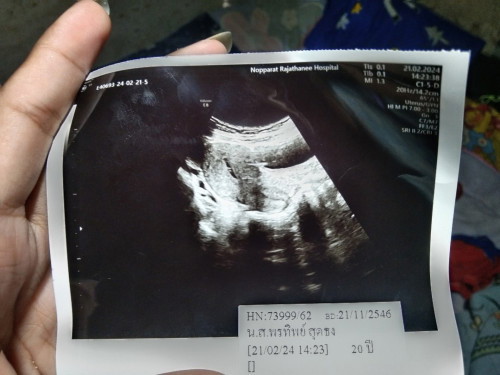

เมื่อวานไปสาธารณสุขเพราะปวดท้อง คัดเต้านม มีเลือดออกเขาให้ตรวจการตั้งครรภ์ขึ้น2ขีดจางมากๆ ส่งตัวไปรพ.วันนี้ขึ้นขีดเดียวอัตซาวด์ตามภาพเลยคะประจำเดือนมาวันที่5กพ.67 หมดวันที่9กพ.67 หมอแจ้งว่าแท้งครบแล้ว มีโอกาสน้องยังอยู่ไหมคะ🥹